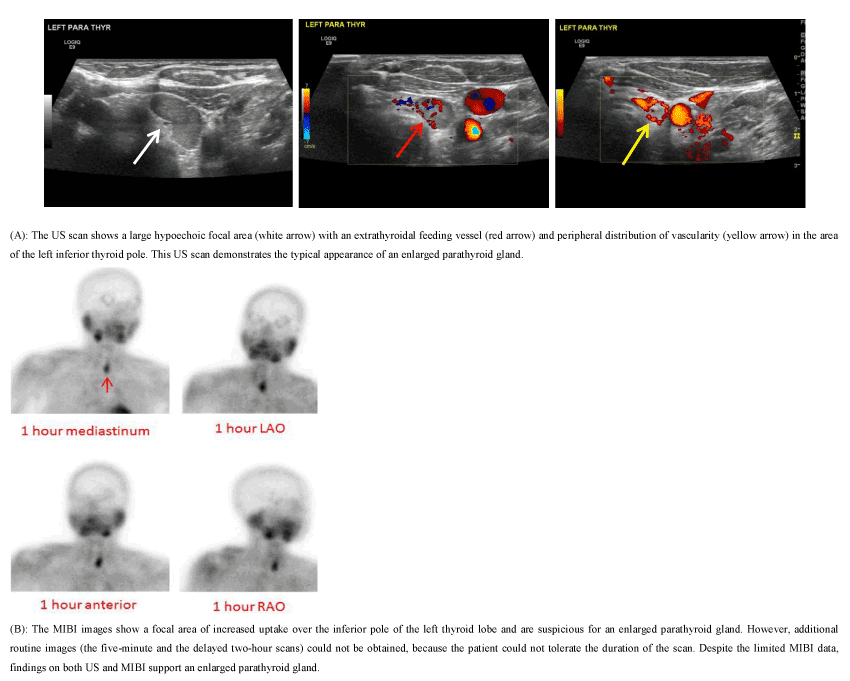

Figure 2. 49-year-old female presented with a PTH level of 1123.5 pg/ml and a calcium level of 12.8 mg/dl.

In 34 of the 56 cases, the parallel use of preoperative MIBI and US resulted in consistent findings between the two imaging modalities. A typical feature of parathyroid adenomas on MIBI is a focal area of persistently increased uptake in the region of the thyroid gland. On US, the characteristic appearance of parathyroid adenomas is a homogeneously hypoechoic focal area with a feeding vessel and a peripheral distribution of vascularity (Figure 2A). The remaining 22 cases demonstrate that the limitations of one modality can be overcome by the advantages of the alternate modality.

The limitations of MIBI include: 1) false-positive findings due to thyroid nodules (Figure 1); 2) false-negative or low confidence results due to the relatively small size of enlarged parathyroid gland(s) (Figure 3); 3) suboptimal results due to body habitus, motion, patient intolerance to lengthy procedures, or an adverse tracer reaction (Figure 2B); 4) information arising from a predominant, hyperfunctioning parathyroid gland that overwhelms the uptake activity from the other non-dominant, enlarged parathyroid glands (Figure 4); 5) the inability to portray an accurate relationship between an enlarged parathyroid gland and its surrounding structures (Figure 5); and 6) the inability to detail concurrent thyroid nodules (Figure 6).